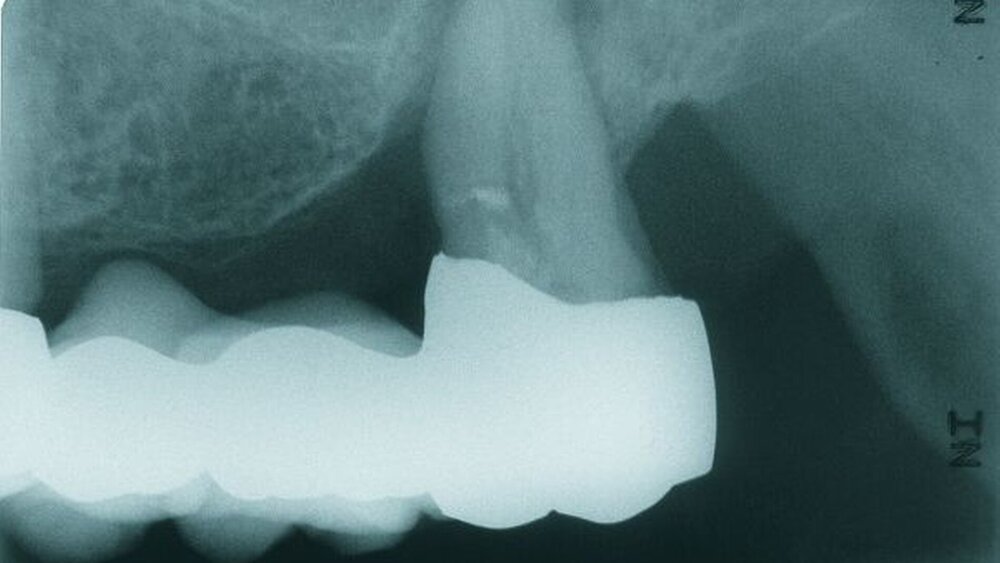

Röntgenbefund

Auf dem vor Anfertigung des Zahnersatzes angefertigten OPG sowie den angefertigten Zahnfilmen der regiones 17 und 27 waren generalisierte horizontale Knochenverluste im Bereich aller verbliebenen Zähne erkennbar. Die Zähne 17 und 27 wiesen zudem vertikale Knocheneinbrüche auf. Eine radiologische Furkationsbeteiligung ließ sich in beiden Fällen nachweisen. Der Zahn 47 war wurzelkanalgefüllt.

Obwohl der Zahn 47 eine radiologisch nicht vollständig bis zum radiologischen Apex reichende Wurzelfüllung aufwies, wurde auf eine Revision der Wurzelfüllung aufgrund einer seit mehr als 15 Jahren bestehenden Beschwerdefreiheit des Patienten und vollständiger Symptomlosigkeit des Zahnes verzichtet [Peak et al., 1994]. Der Patient wurde über diese Sachverhalte ausführlich aufgeklärt und erklärte sich mit dem Belassen der Wurzelfüllung einverstanden.